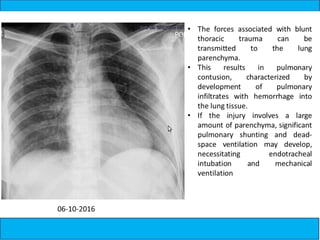

A medical document discusses hypoxia following a road traffic accident. It describes four types of pulmonary contusion caused by direct chest compression, shearing against vertebral bodies, fractured ribs directly injuring the lung, or tearing of lung parenchyma due to prior adhesions. The document also mentions management of pulmonary contusion.